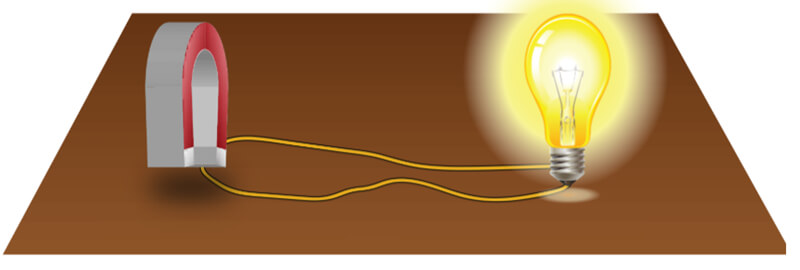

In 1821, following the discovery of the phenomenon of electromagnetism by the Danish chemist Ørsted, Faraday built two machines to produce what he would call an electromagnetic rotation: the continuous circular movement of a magnetic force around a wire is the principle of an electric motor. In this experiment, if we rotate a magnetic field, shown here as a u-shaped magnet, it creates an electric current, to power a light bulb in our example.

This is still the way we generate electricity today. The magnet used is rotated as a result of the power created by the action of water such as with in hydroelectric power plants, with heat in conventional or nuclear power plants, with wind as in windmills or with mechanical effort, dynamo.

A rotating current generates a magnetic field and vice versa: a rotating magnetic field generates an electric current. In emergency situation, a Quench can be provoked to stop the magnetic field of a superconductor magnet. Now it’s time to take your quiz and issue your certificate. Please proceed to the quiz for module one where you will find additional instructions.

The idea of MRI came from a discovery in 1831! Michael Faraday discovered that when there was a change in magnetism within a coil of wire, a voltage resulted. When the bar magnet moves into the closed-loop, the voltage increases. When the bar magnet is removed the voltage goes down. We refer to the force created as the electromagnetic force.

Of course, Faraday had no idea that at some time in the future, we would use this technology to create electromagnetic engines, OR use the same principles to create images of the internal structures of human anatomy. The MR signal that results during an MRI examination is a small electrical current induced by the receiver coil by the precession of the net magnetization during the MR scan.

- A rotating current generates a magnetic field and vice versa: a rotating magnetic field generates an electric current